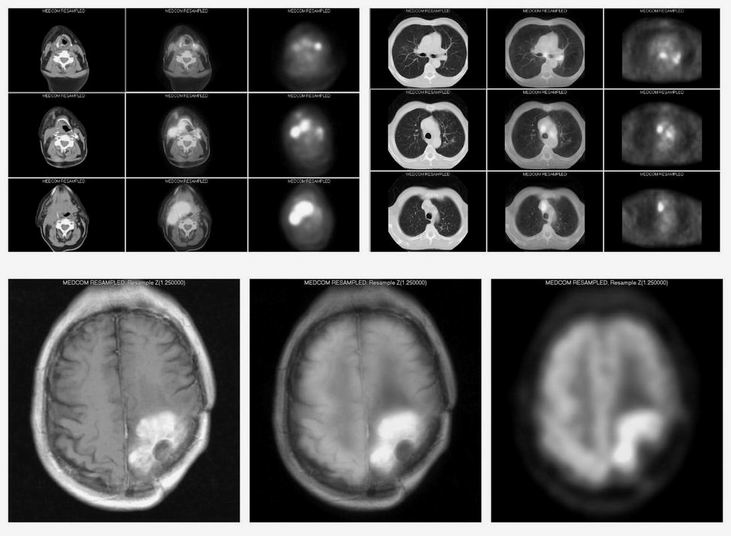

Příklady obrazů

Od února 2004 provádíme na pracovišti softwarovou fúzi obrazů PET / CT a PET / MR.

Vzhledem k tomu, že data CT nebo MR pocházejí z rozličných pracovišť, nepoužíváme vnějších anatomických značek.